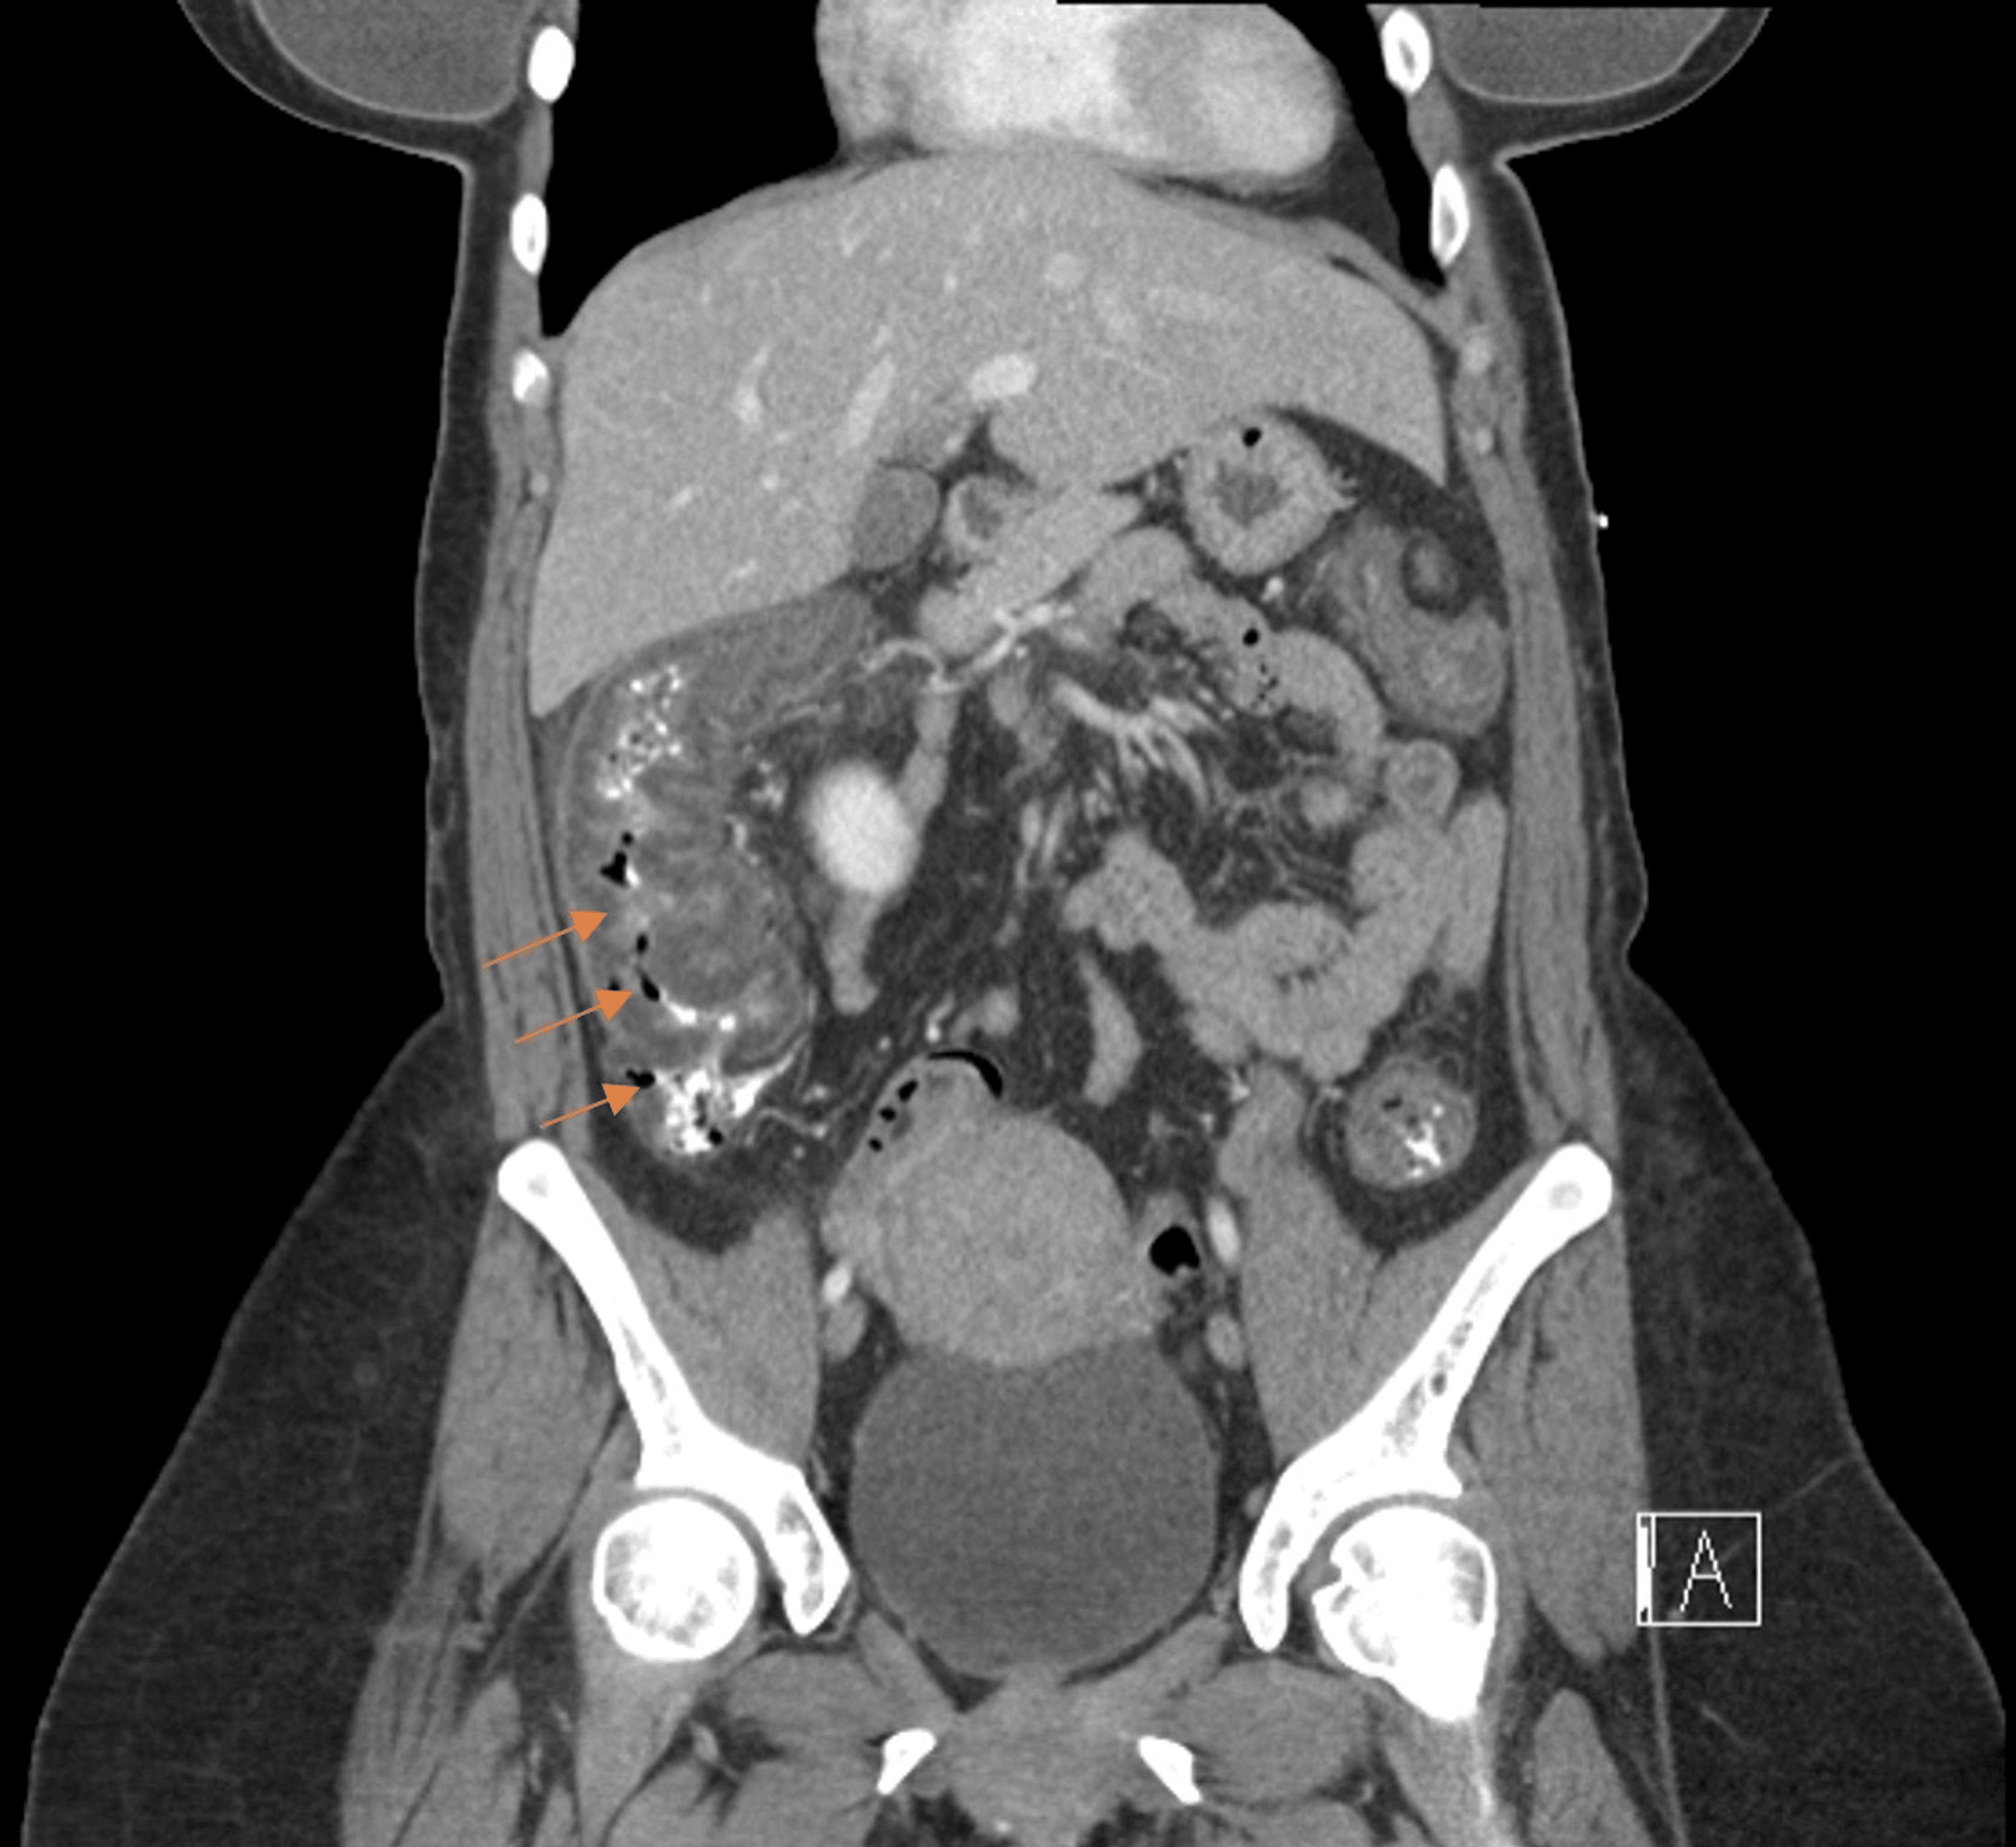

From www.cureus.com

Cureus Ischemic Colitis in a Young Female Following Herbal Supplement Ingestion Ischemic Colitis Natural Treatment Ischemic colitis is a serious health condition that affects as much as 1 in ever 2, 000 people who make a visit to the hospital’s emergency room every year; Ischemic colitis manifests as bloody diarrhea, after the colon has been injured in some way. Pain in the lower left abdomen is common. Ayurveda aims to restore balance to the doshas. Ischemic Colitis Natural Treatment.